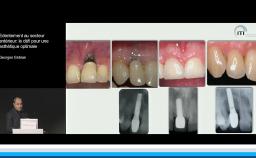

Tous les types d’implants peuvent être utilisés en secteur antérieur, mais l’utilisation de connexions au niveau osseux offre plus de latitude sur le placement de l’implant et sur la réhabilitation prothétique. Afin de limiter les proximités entre implants et entre dents et implants, l’utilisation d’implants de faible diamètre et la réduction du nombre d’implants sont des options à considérer.